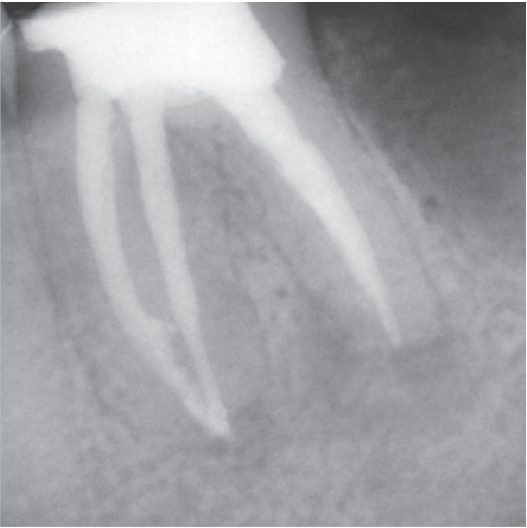

After

After Root Canal treatment